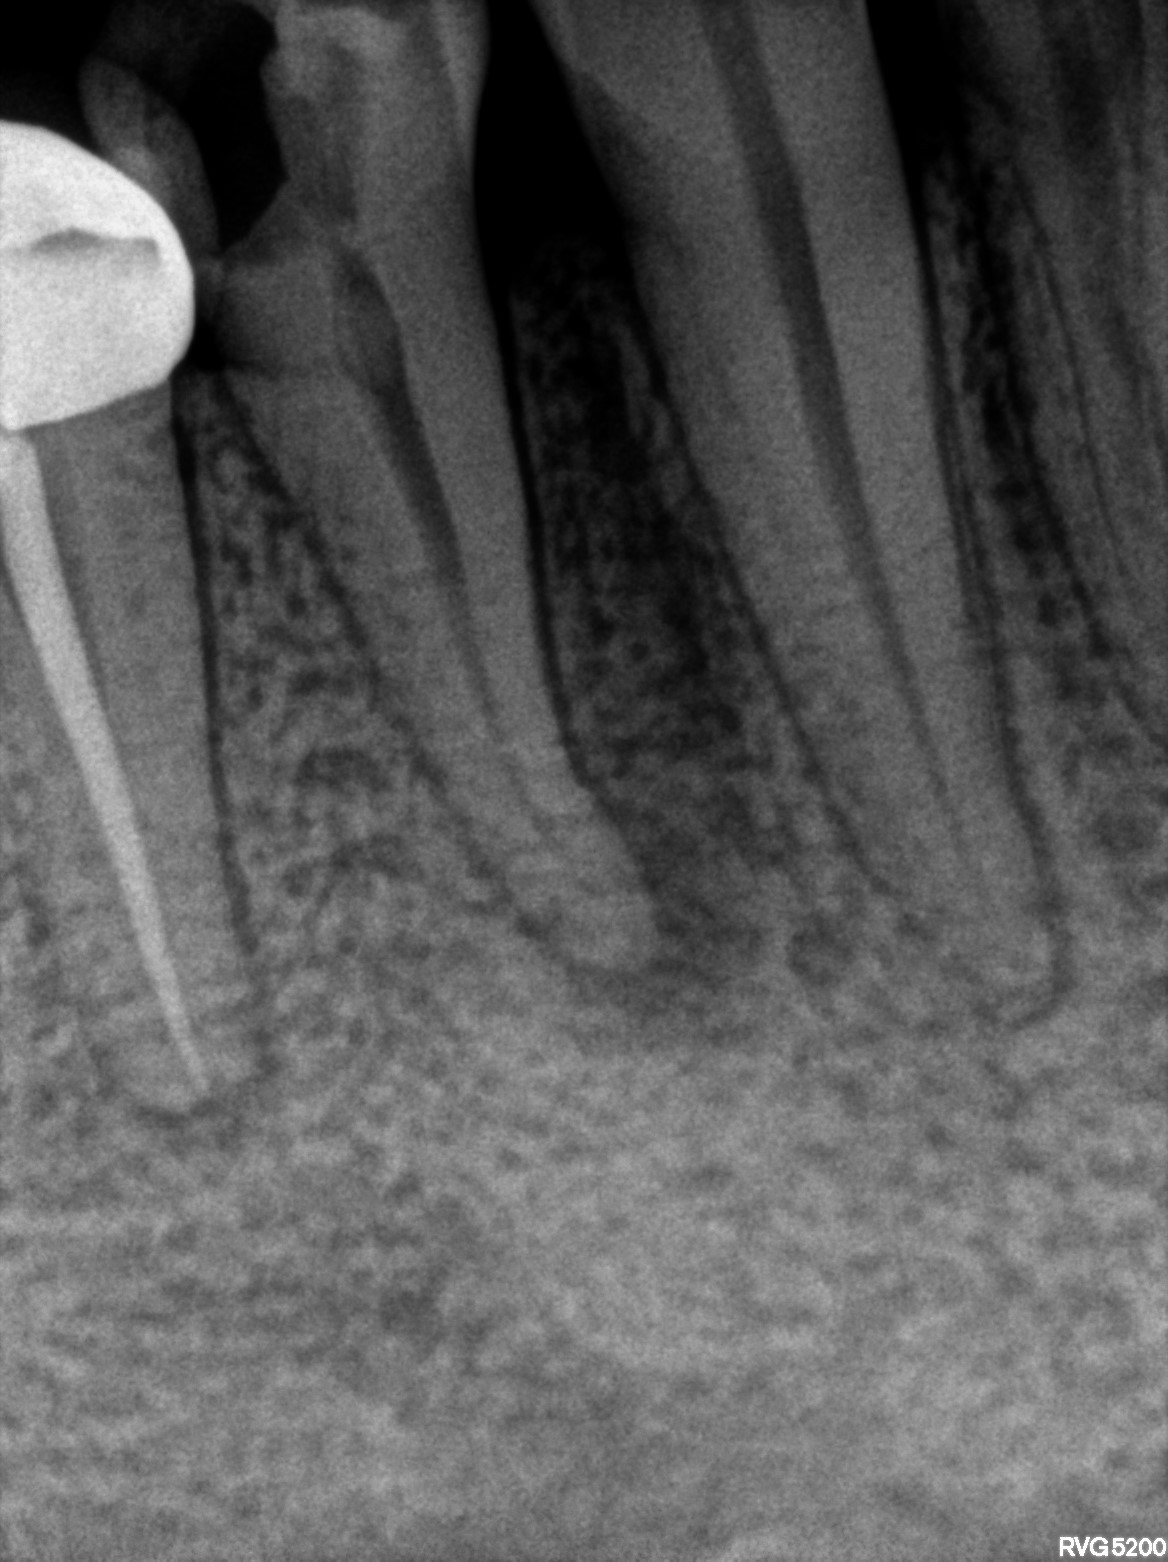

Dental Radiographs FHIR: DocumentReference · LOINC 24641-7

xray_1772203508_0.jpg

24641-7

xray_1770308600_0.jpg

xray_1770308600_1.jpg